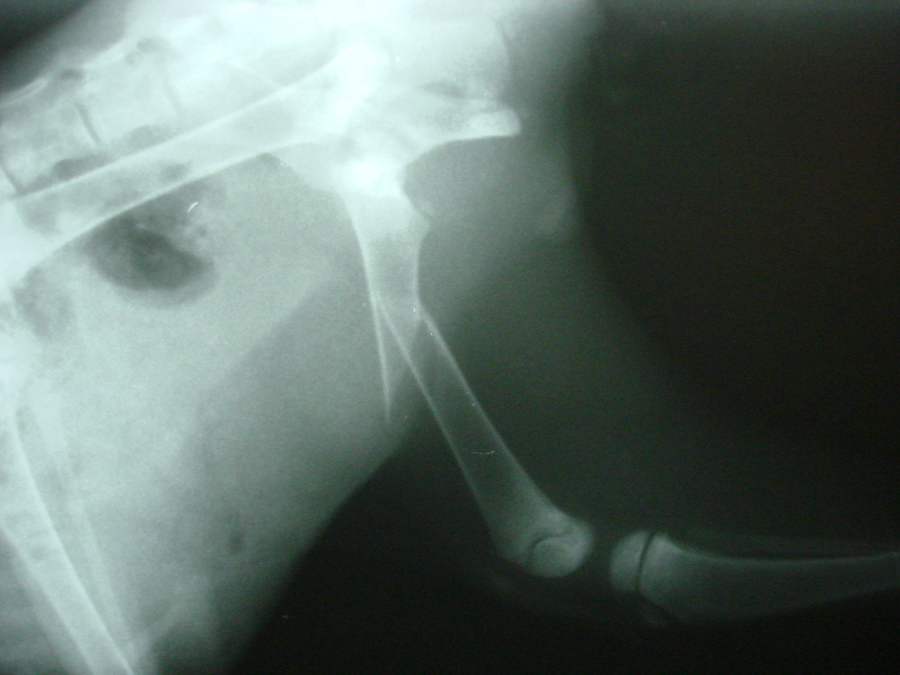

Letošní rok bylo na naše pracoviště přivedeno malé cca tříměsíční kotě, které nešťastnou náhodou vypadlo majitelům z okna. Při pádu si kotě bohužel zlomilo diafýzu stehenní kosti levé pánevní končetiny.

Fraktura stehenní kosti kotěte1

Fraktura stehenní kosti kotěte2